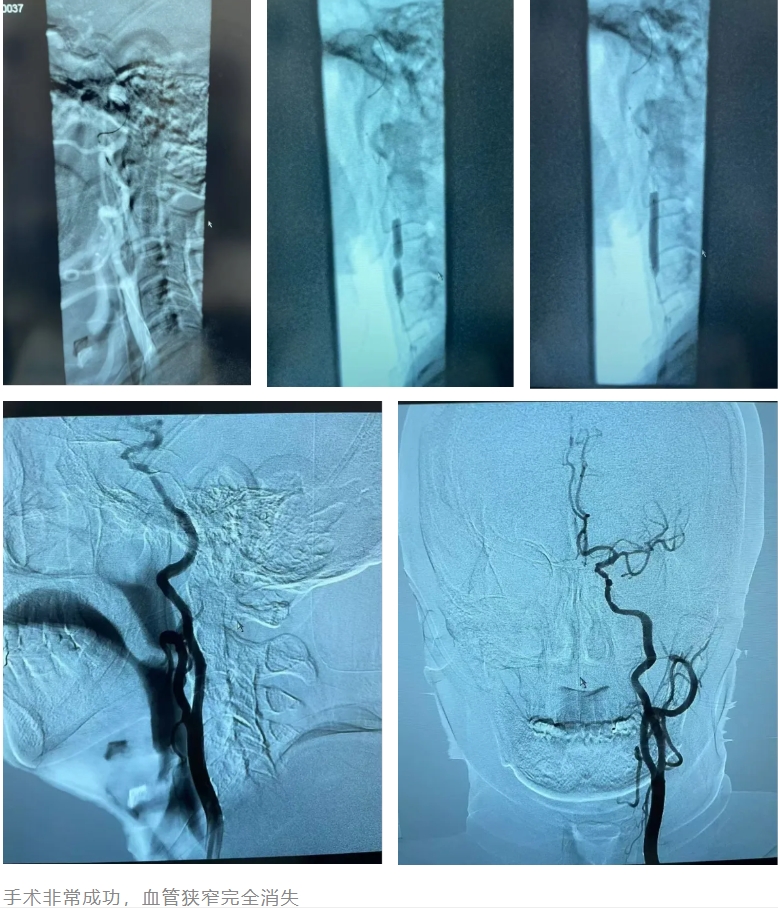

隨后,介入科為潘先生進行全腦血管造影術(shù),進一步明確了右側(cè)頸內(nèi)動脈閉塞,左側(cè)頸內(nèi)動脈近端狹窄程度高達 99%。根據(jù)檢查結(jié)果,醫(yī)院制定的了詳細周全的介入治療方案。

隨后,介入科團隊在局麻下為潘先生實施了左側(cè)頸內(nèi)動脈狹窄保護傘下球囊擴張 支架植入術(shù)。手術(shù)非常成功,患者血管狹窄完全消失。